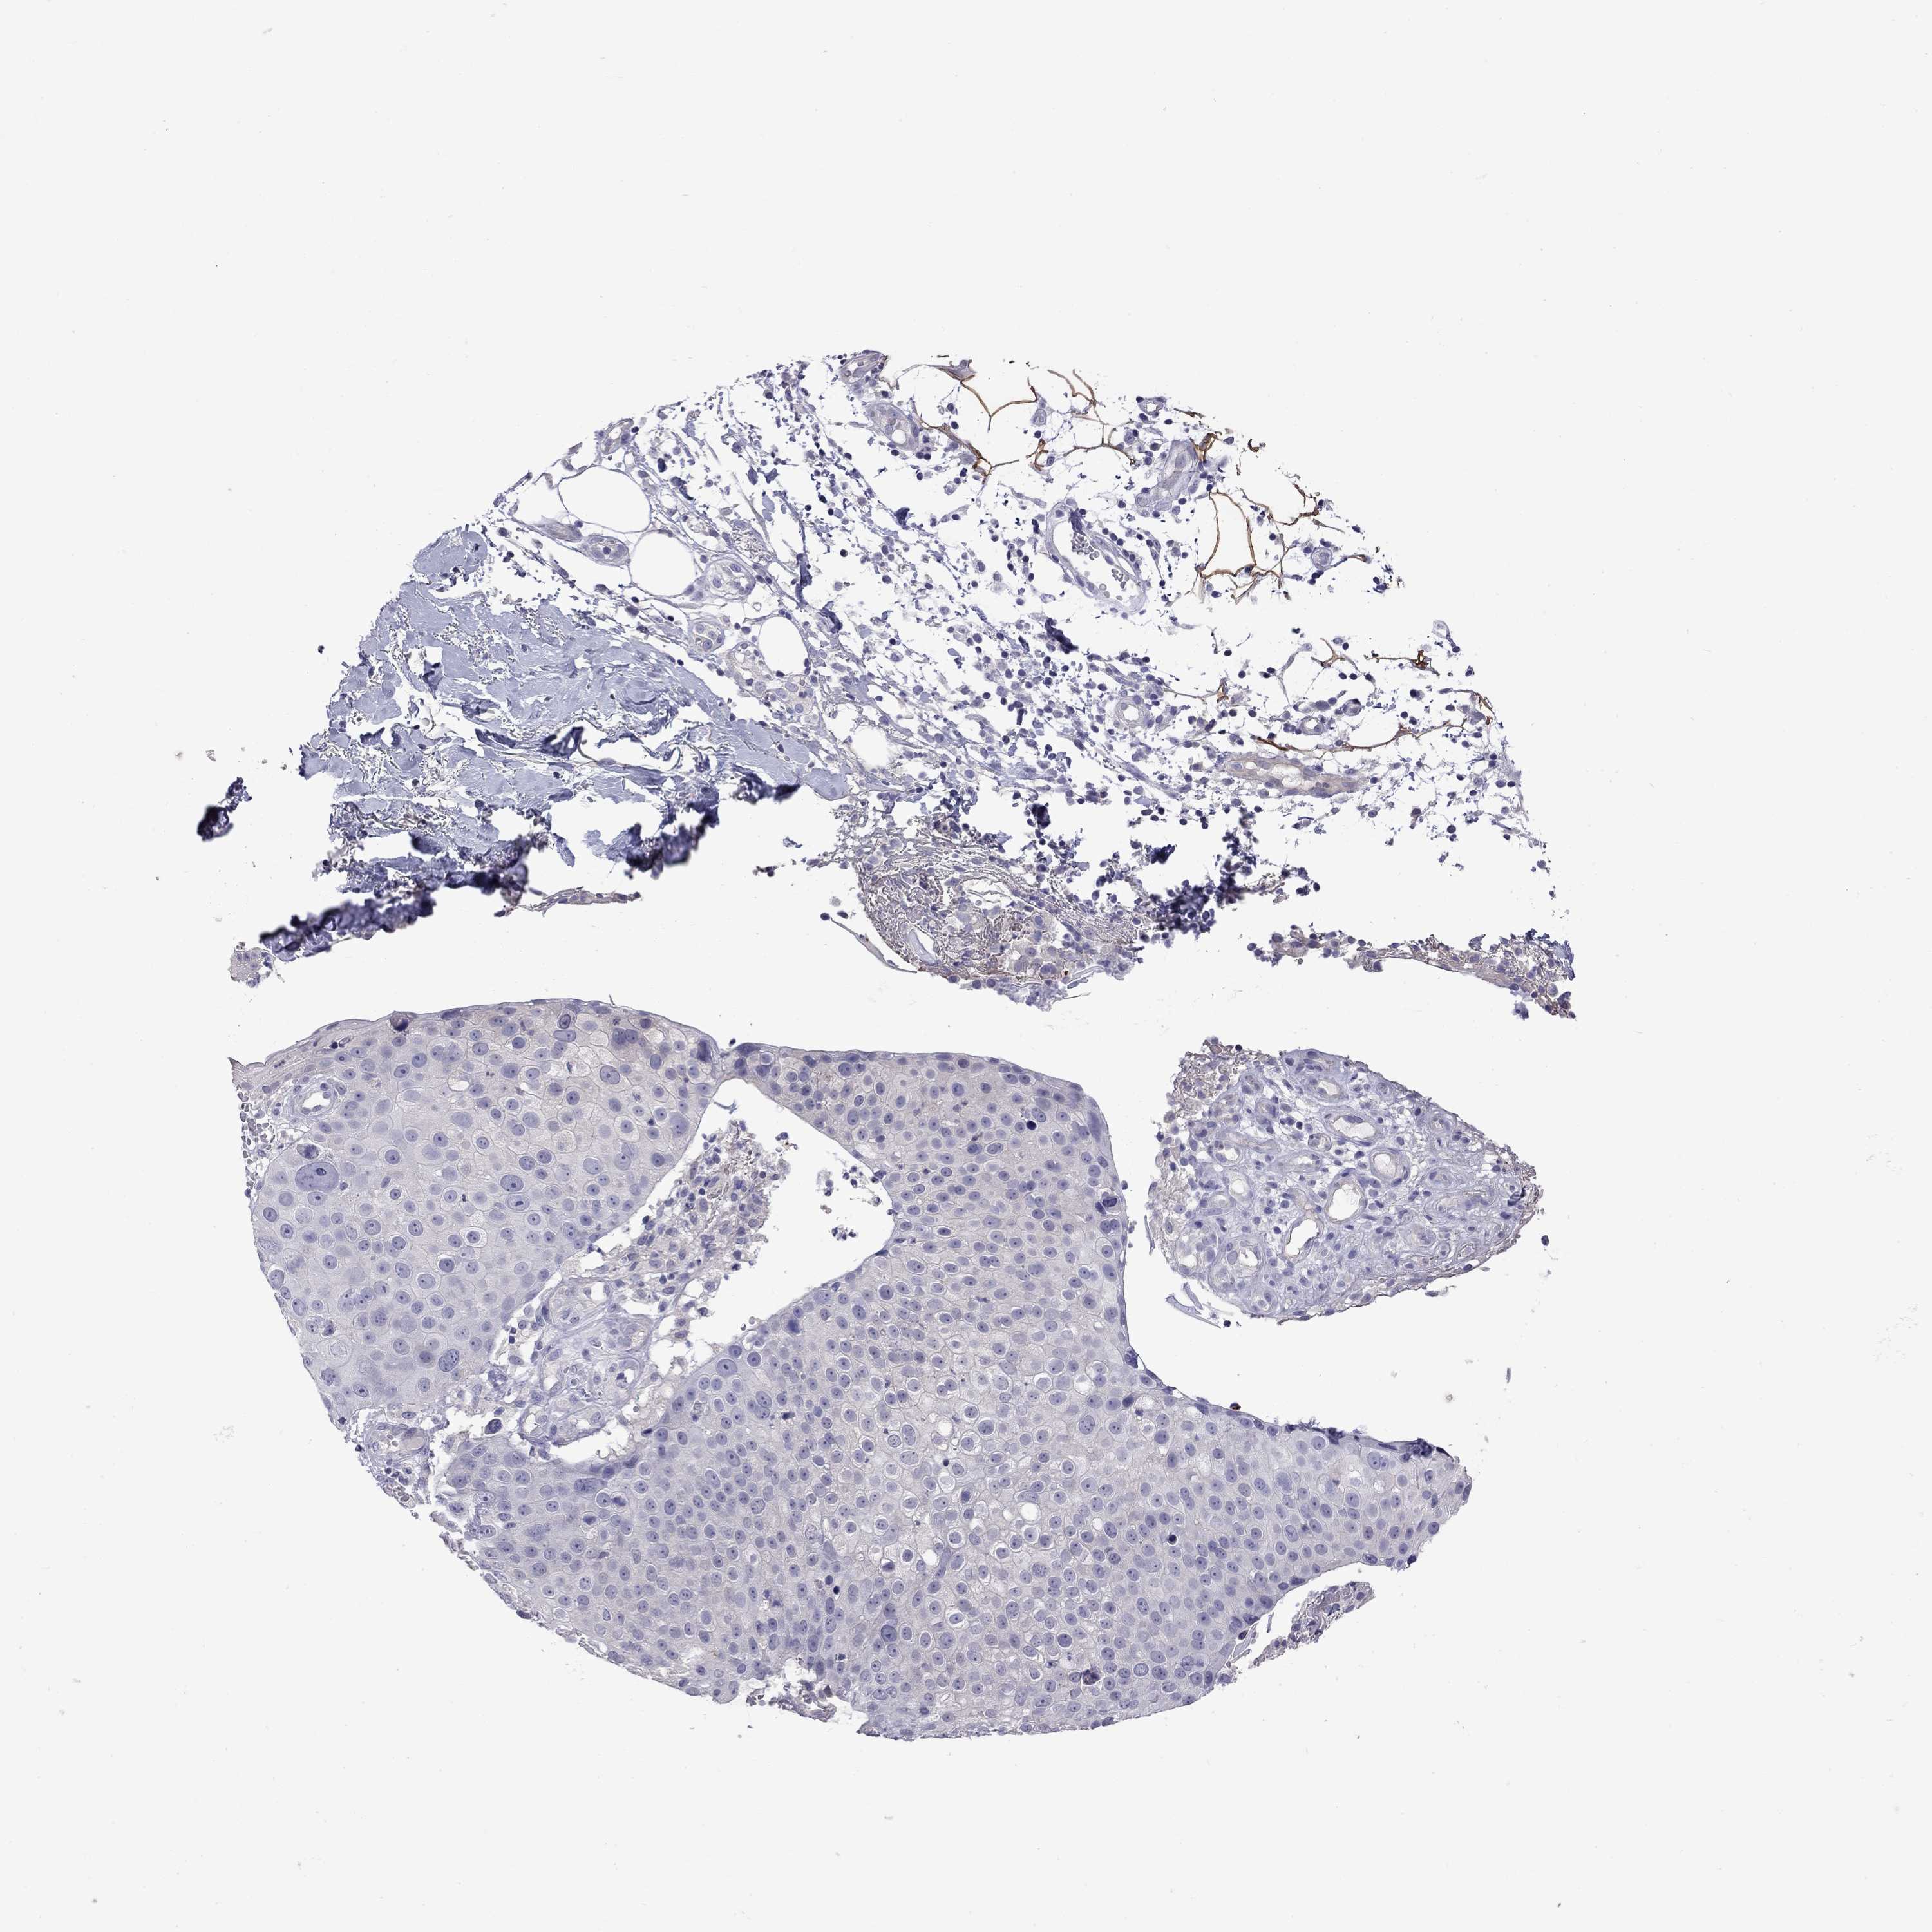

CANCER SKIN CANCER Show tissue menu

Basal cell and squamous cell cancer

SKIN CANCER - Protein expressioni

A mouse-over function shows sample information and annotation data. Click on an image to view it in a full screen mode. Samples can be filtered based on level of antibody staining by selecting one or several of the following categories: high, medium, low and not detected. The assay and annotation is described here.

Each image is clickable and will lead to virtual microscopy that enables deeper exploration of all samples and also displays staining intensity scores, fraction scores and subcellular localization as well as patient and tissue information for each sample.

Antibody HPA076844

Basal cell carcinoma

Squamous cell carcinoma, NOS